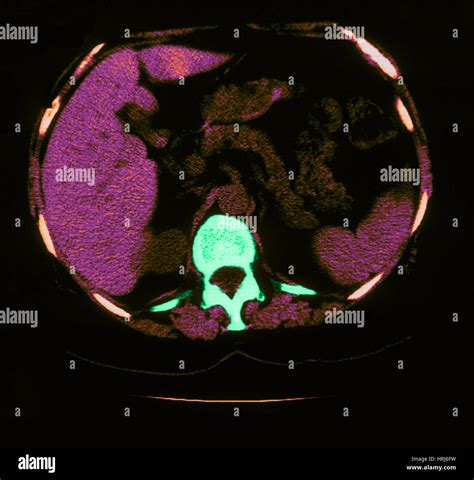

• CT Scan: A computed tomography (CT) scan provides detailed images of the lungs and can help identify the location and extent of the calcification.